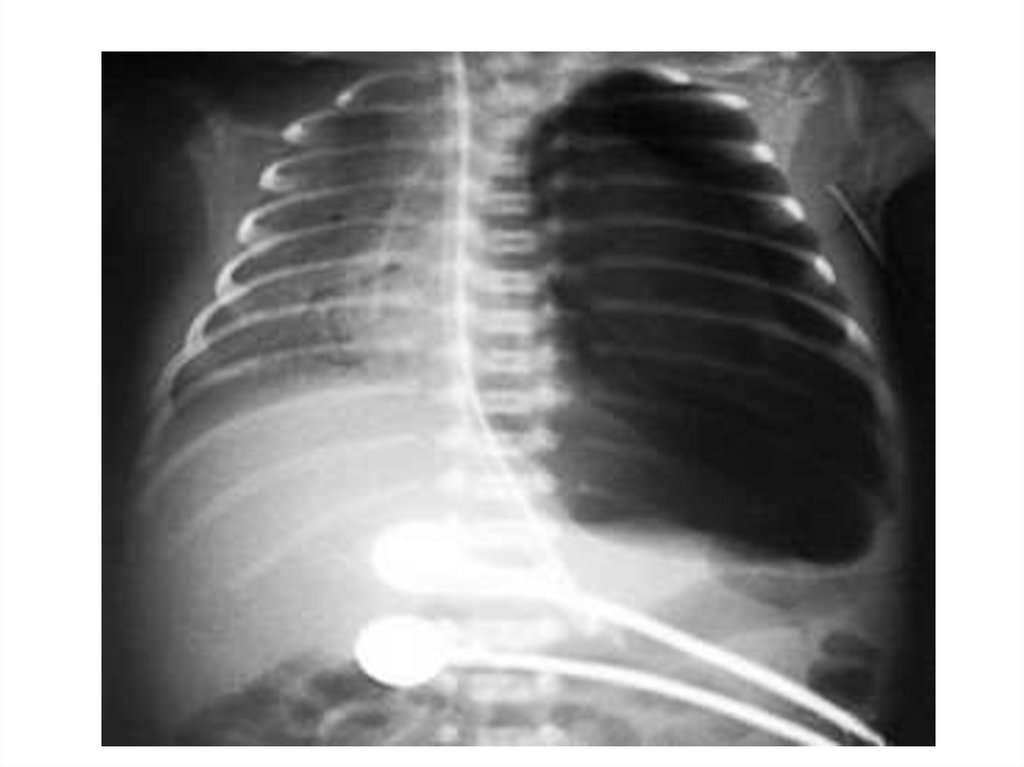

Гидроторакс

Пневмоторакс Гидроторакс